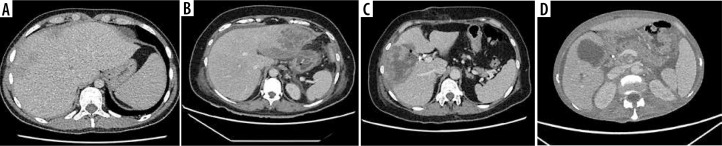

Results: The contrast enhancement pattern on CEUS matched post-contrast CT. Lesion size detected by CEUS ranged from 1.16 cm to 15.33 cm (median 5.74 cm). CT classified lesions into four types: I (tumor-like) - 2, II (honeycomb) - 5, III (lacunar) - 23, IV (cystic-like) - 34. CEUS fully agreed with these classifications. B-mode missed two type I lesions. For type III abscesses, agreement with CEUS was perfect (κ = 1, 100%), and moderate with B-mode (κ = 0.50, 79.7%). For type IV abscesses, agreement with CEUS was perfect (κ = 1, 100%), and high with B-mode (κ = 0.88, 93.75%). Pus enhancement remained stable (± 15 dB), while the abscess pouch background varied (± 11 dB to ± 6 dB). The Mann-Whitney U test confirmed these observations (arterial: p = 1.02e-14, portal: p = 3.79e-12, late venous: p = 4.53e-13). No significant difference in enhancement values was found based on abscess size (> 4 cm vs. < 4 cm).

Conclusions: CEUS is superior to B-mode for diagnosing and monitoring HA, offering clearer views of the abscess pouch, septa, and liver parenchyma. The purulent part lacks contrast, allowing accurate assessment. CEUS can replace CT for monitoring and aid in patient selection for percutaneous intervention.